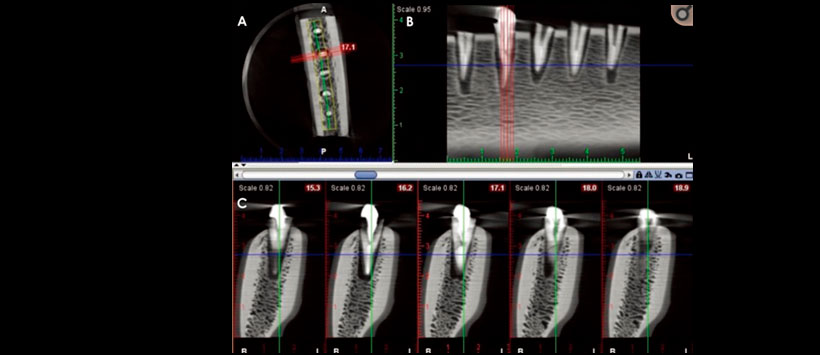

El posicionamiento periférico del objeto sin el algoritmo MAR produjo la sensibilidad más alta para el primer observador (66.7%). Para el segundo y tercer observador, una posición central mejoró la sensibilidad, con o sin el algoritmo MAR. En presencia de postes metálicos, la posición central del objeto en el FOV aumentó significativamente la sensibilidad y la precisión del diagnóstico en comparación con la posición periférica. (Figura 1)

Siendo la precisión diagnóstica fue mayor con el posicionamiento central (Figura 2) que con el posicionamiento periférico, independientemente de si se aplicó el algoritmo MAR (Figura 3). Sin embargo, el efecto del algoritmo MAR fue más significativo con el posicionamiento central que con el posicionamiento periférico del objeto en el FOV. La experiencia clínica y la experiencia de los observadores pueden servir como un factor de confusión a este respecto.